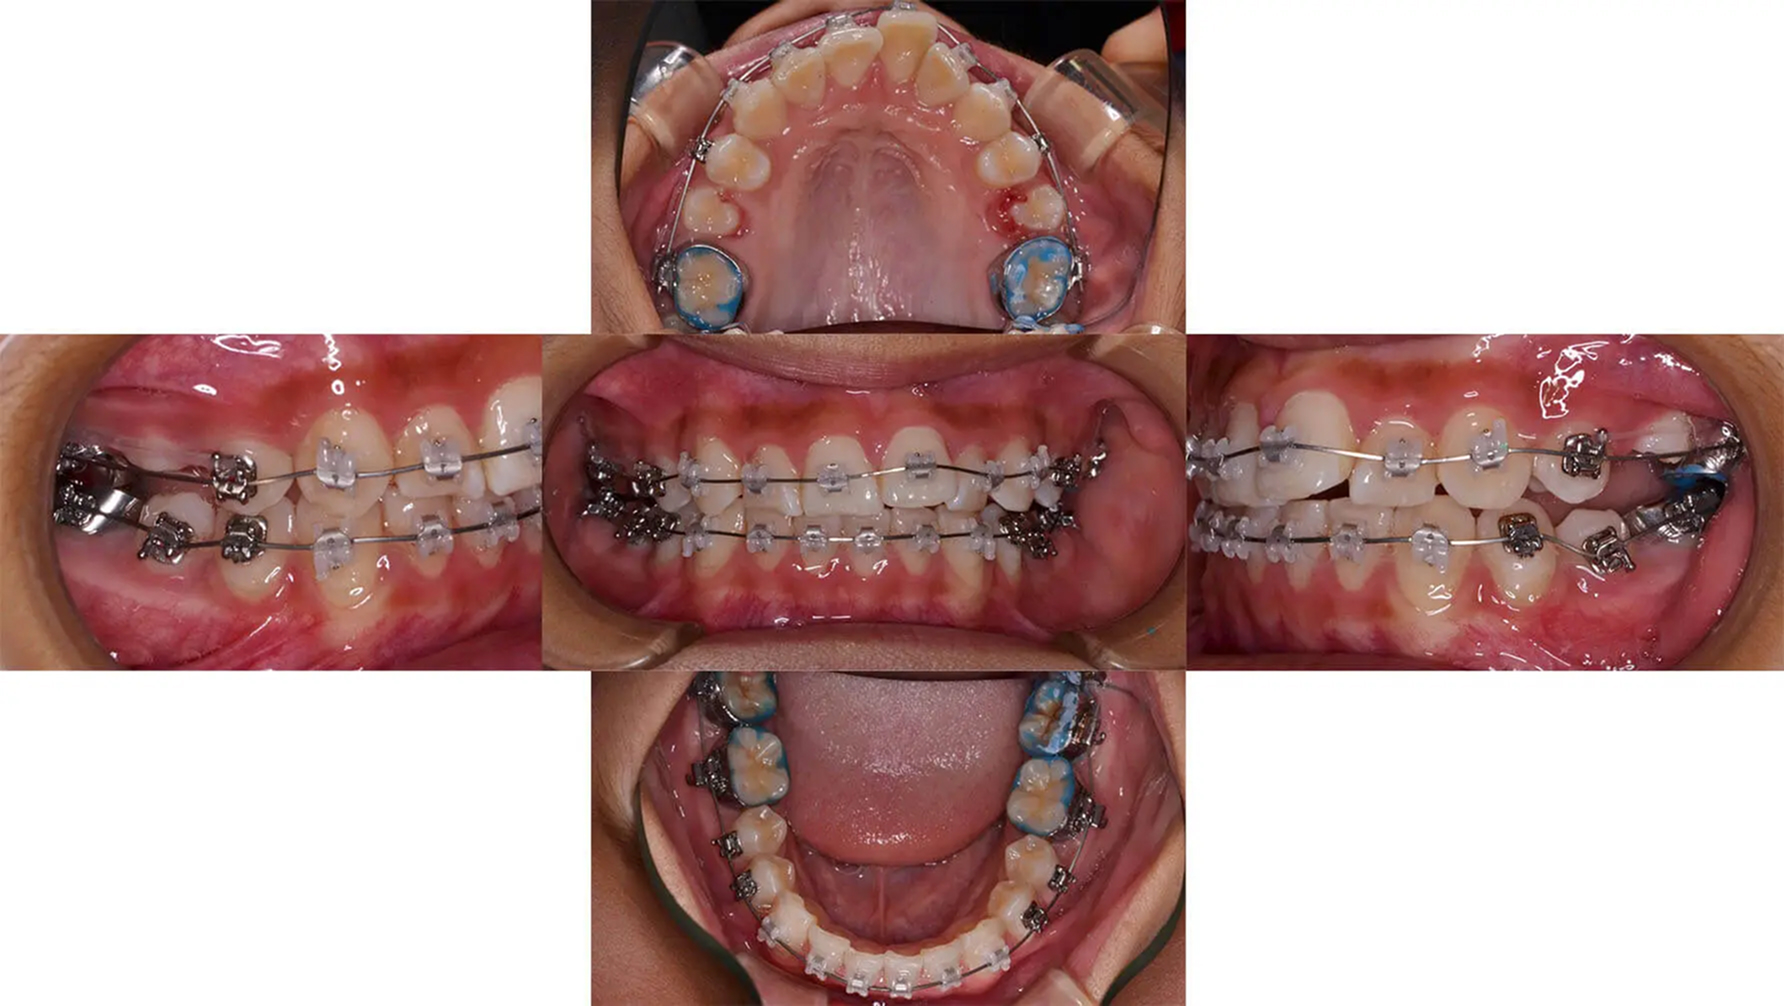

小学生のころから来院されていて、出っ歯を気にしていました。中学生になり左側中切歯がさらに前方に出てきたので、それを機会に矯正治療を開始しました。出っ歯の場合、大きく後方に移動するには小臼歯抜歯が必要です。しかし、今回は診査の結果と本人の希望により、抜歯なしで行うことにしました。非抜歯でしたが前歯が揃い、ある程度後方に移動できました。3年後、後戻りは最低限で経過しています。

初診 2015.5.29

矯正治療開始 2015.6.19

ファイナル 2016.8.31

治療3年後 2019.8.23

| 主訴 | 前歯1本前に出ている |

| 診断 | 左側アングル1級、右側アングル2級叢生を伴う上顎前突 |

| 矯正方法 | ゴムメタルワイヤーを用いたマルチブラケット |

| 矯正期間 | 15か月・17回 |

| 費用 | 690,000円(税別) |

| 調整料 | 月1回 5,000円(税別) |